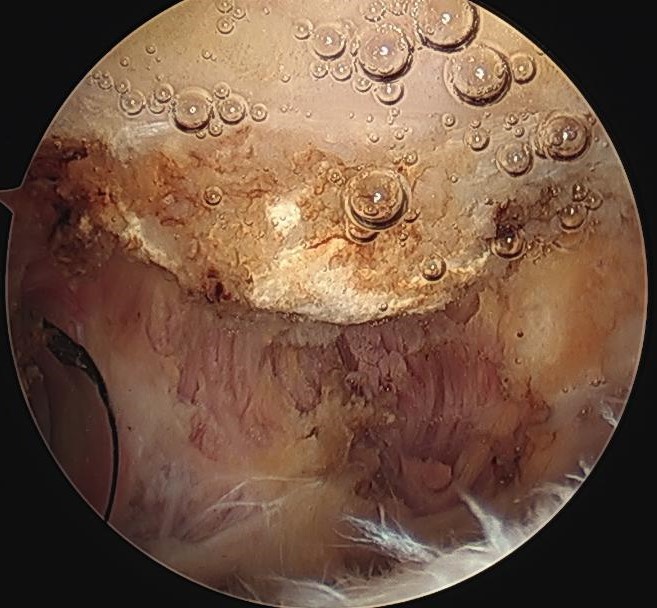

Arthroscopic acromioplasty

Technique

Beach chair / lateral

- posterior viewing portal subacromial space

- lateral working portal

- bursectomy with shaver

- electrocautery to release / resect CA ligament

- use burr to perform anterior acromioplasty

CA ligament above shaver and cuff

Large acromial spurs

Spur resection